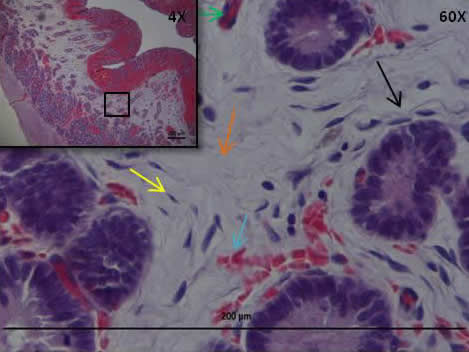

(Obj. 4X y 60X H&E). Corte de endometrio con ESC en el cual se pueden observar fibrocitos (flecha amarilla), hiperplasia de tejido conectivo (flecha naranja), edema (flecha negra), hemorragia (flecha celeste), hiperemia (flechas verdes).